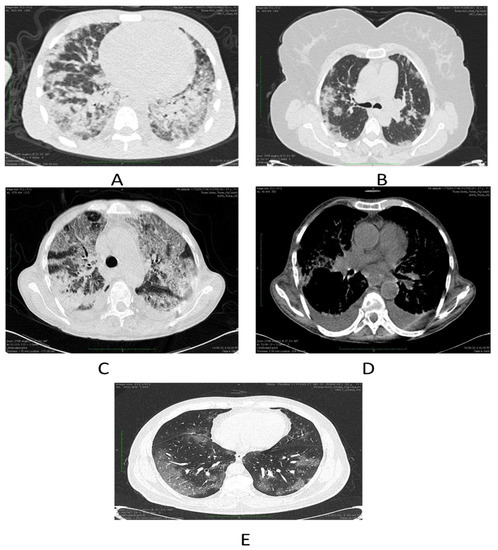

| Chest Computed Tomography (n = 152) | |||

| COVID-19 suggestive | 110 (72.37) | ||

| Pleural thickening | 3 (1.97) | ||

| Ground-glass opacity | 110 (72.37) | ||

| Septal thickening | 53 (34.87) | ||

| Crazy paving | 30 (19.74) | ||

| Subpleural consolidation | 30 (19.74) | ||

| Pleural effusion | 36 (23.68) | ||

| COVID-19 phenotypes (n = 110) | |||

| Phenotype 1 | 52 (47.27) | ||

| Phenotype 2 | 25 (22.73) | ||

| Phenotype 3 | 2 (1.82) | ||

| Distribution (n = 152) | |||

| Peripheral | 69 (45.39) | ||

| Diffuse | 21 (13.82) | ||

| Central and peripheral | 21 (13.82) | ||

| Central | 6 (3.95) | ||

| Normal | 36 (23.68) | ||

| CT total severity score (Mean ± SD) | 11.63 ± 4.06 | ||

| Mild | 77 (50.66) | ||

| Moderate | 68 (44.74) | ||

| Severe | 7 (4.61) | ||